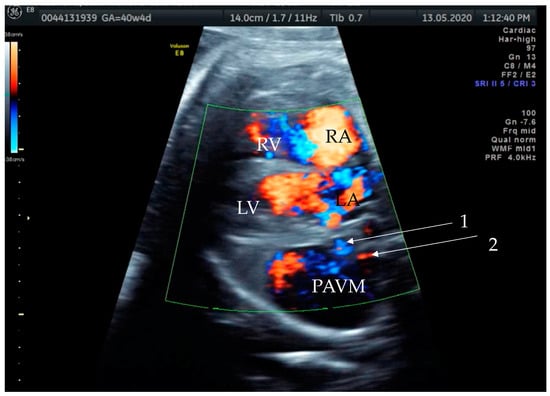

Figure 2. Prenatal transabdominal color Doppler mode ultrasound picture with visible bidirectional flow in the cystic structure. Arrow 1—venous part of the feeding vessels with connection to the left atrium, Arrow 2—arterial part of the connection to the left main branch of the pulmonal artery, RV—right ventricle, LV—left ventricle, RA—right atrium, LA—left atrium, and PAVM—pulmonary arteriovenous malformation. Due to the gestational age, it was difficult to distinguish the two feeding vessels in one picture, as shown in the last prenatal picture (Figure 3).